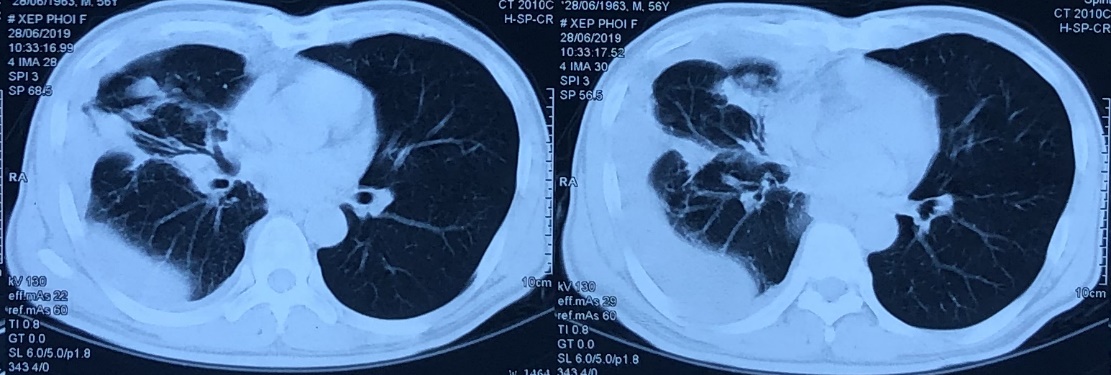

– Chụp cắt lớp vi tính lồng ngực: U thùy dưới phổi phải, tràn dịch màng phổi phải

Hình 1: Hình ảnh chụp cắt lớp vi tính lồng ngực